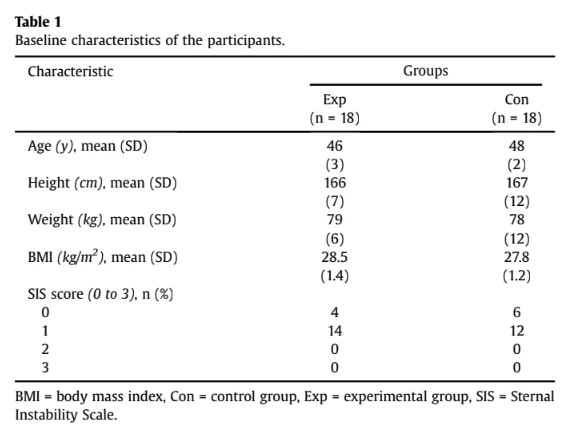

本文采用随机对照试验设计,研究了疝切除术后躯干稳定运动的有效性。 通过胸骨正中切口接受心脏瓣膜手术的 40-50 岁女性在术后一周被招募。 排除标准包括既往胸外科手术史、糖尿病或未控制的高血压等严重疾病,以及可能影响物理治疗的疾病。

研究对象包括 36 名经超声波检查确认患有急性胸骨不稳的女性。 基线特征显示有两组具有可比性。 他们的基线胸骨分离度为 0.23 厘米